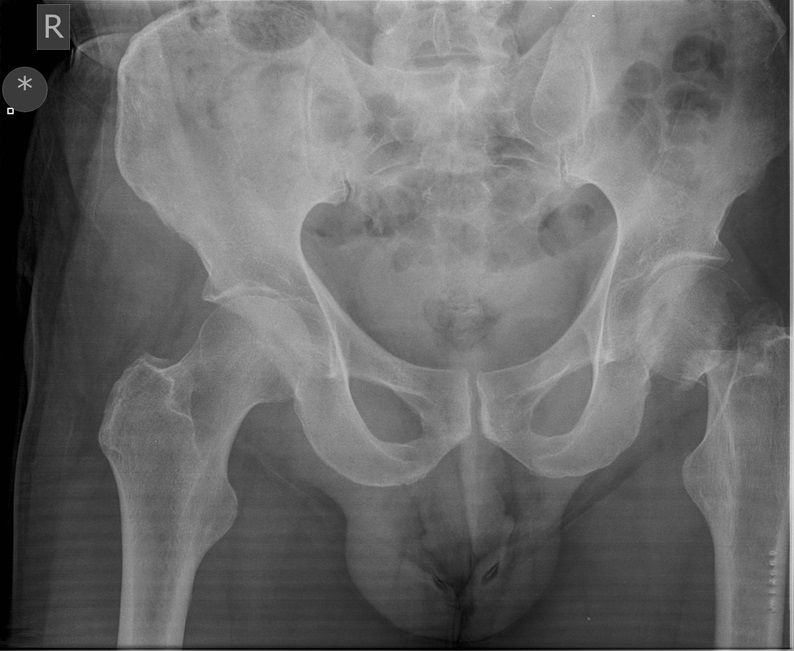

Question 2

Question

Which operation would you perform?

Answer

• THR

• Hemiarthroplasty